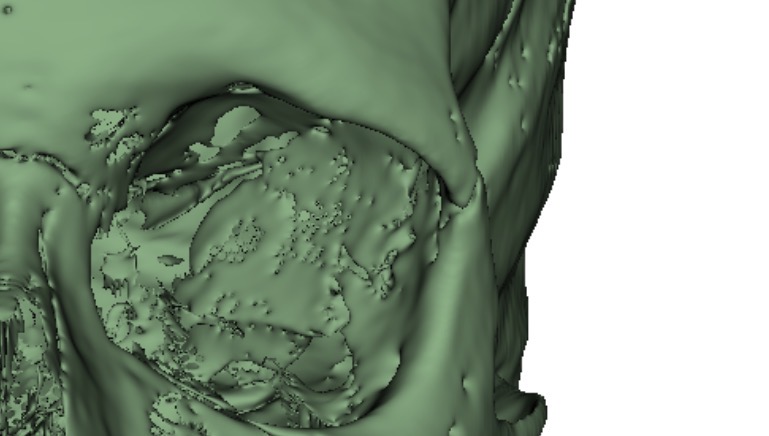

I have finished doing a helical CT scan in a hospital (had to larp that I had breathing problems etc quite an insane xp tbh)

This is the side of my recessed face btw if anyone was curious.

I have finished doing a helical CT scan in a hospital (had to larp that I had breathing problems etc quite an insane xp tbh)

This is the side of my recessed face btw if anyone was curious.